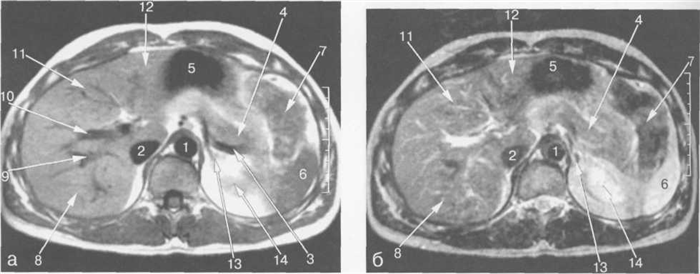

Рис. 11.14. МРТ брюшной полости на уровне ворот селезенки.

1 — аорта; 2 — нижняя полая вена; 3 — левая желудочная артерия; 4 — селезеночная артерия; 5 — желудок; 6 — селезенка; 7 — толстая кишка; 8 — хвост поджелудочной железы.

Рис. 11.15. МРТ брюшной полости в аксиальной плоскости на уровне желчного пузыря.

1 — аорта; 2 — нижняя полая вена; 3 — селезеночная вена; 4 — верхняя брыжеечная артерия; 5 — желчный пузырь; 6 — левый надпочечник; 7 — правый надпочечник; 8 — левая почка; 9 — кортикальный слой левой почки.

Рис. 11.16. MPT брюшной полости в аксиальной плоскости на уровне головки поджелудочной железы.

1 — аорта; 2 — нижняя полая вена; 3 — верхняя брыжеечная артерия; 4 — верхняя брыжеечная вена; 5 -головка поджелудочной железы; 6 — верхний полюс правой почки; 7 — левая почка; 8 — левая почечная артерия; 9 — общий желчный проток.